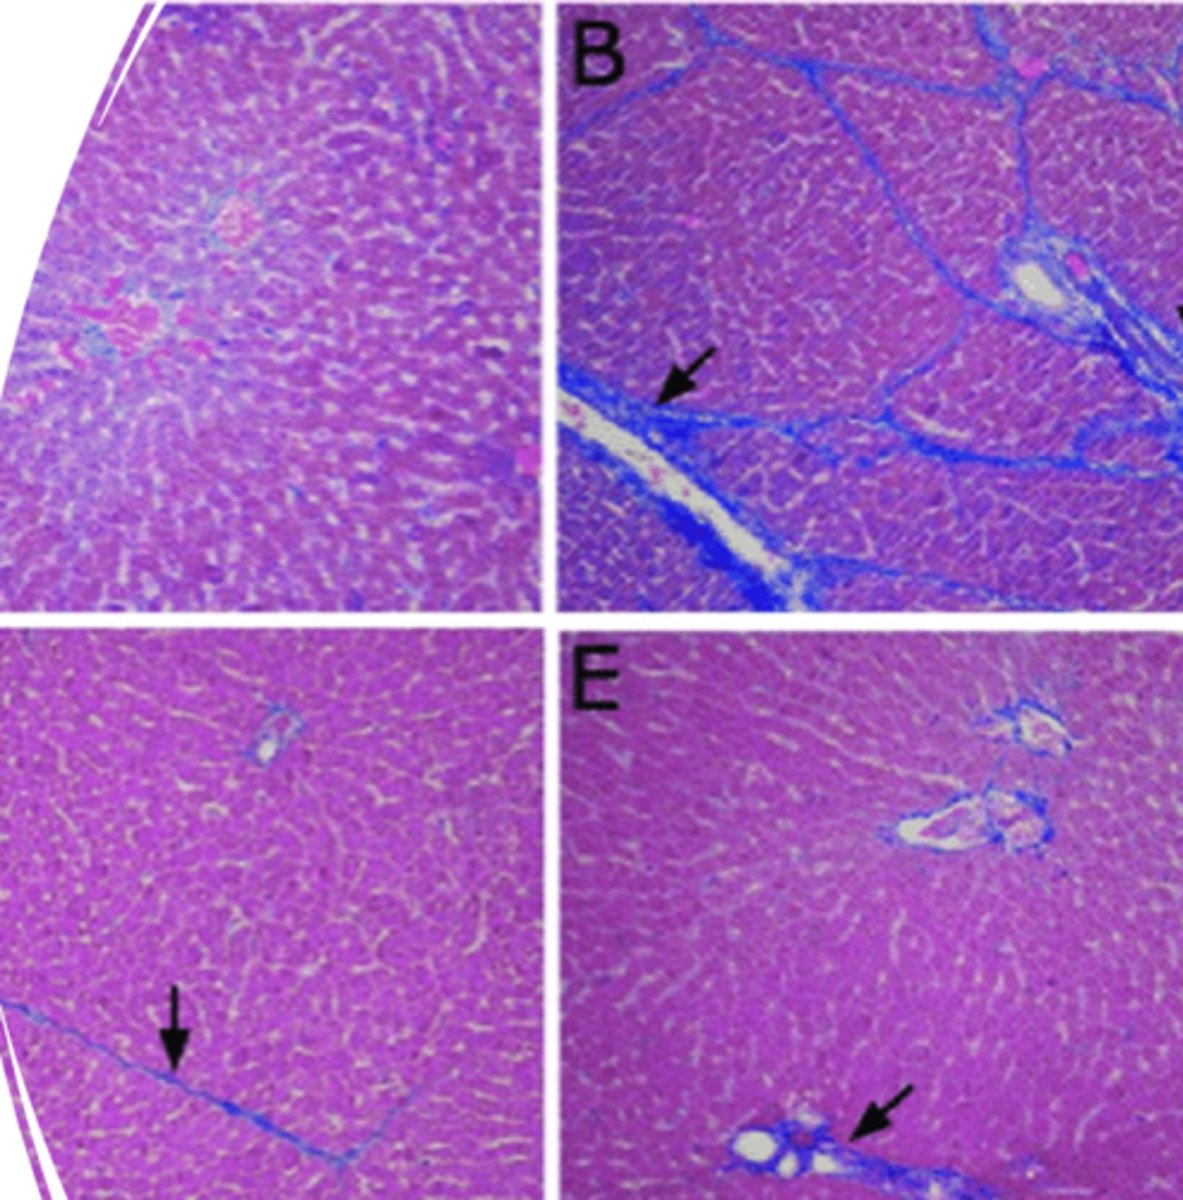

Zonal Hepatocellular degeneration

-pale

-enlarged margins

increased friability

What kind of degeneration is this?

Fibrosis

What is indicated in this image that is a result of chronic liver injury?